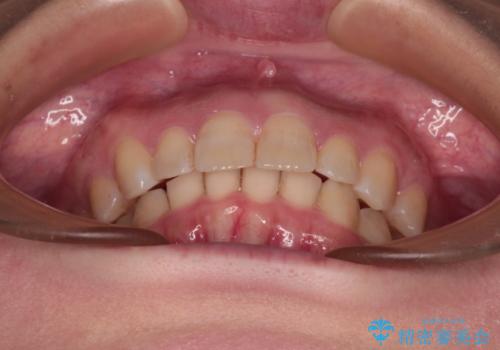

- 上の前歯の出っ歯と前歯の深い咬み合わせを治したいとのことで来院された患者様です。

上顎の歯は後方移動とIPR(歯と歯の間を削る)によって口元が引っ込むように、下顎は歯列全体の拡大とIPRによって上顎とバランスよく咬み合うように設計し、インビザラインにより治療を行うこととしました。

上顎歯列の後方への移動量が多く、右側の奥歯の咬み合わせを改善する必要もあったため、治療には長期間を要しました。